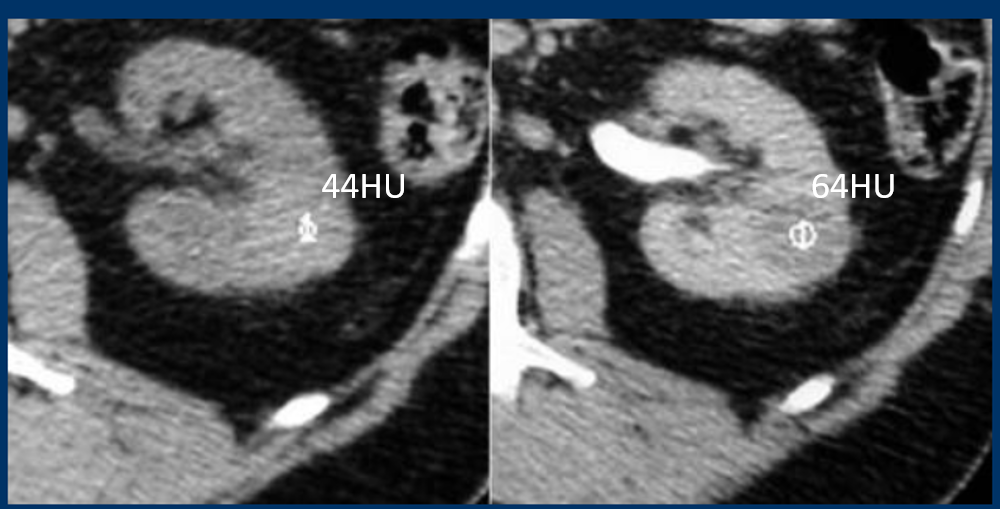

is this mass enhancing?

yes!

new finding. Management?

excise it